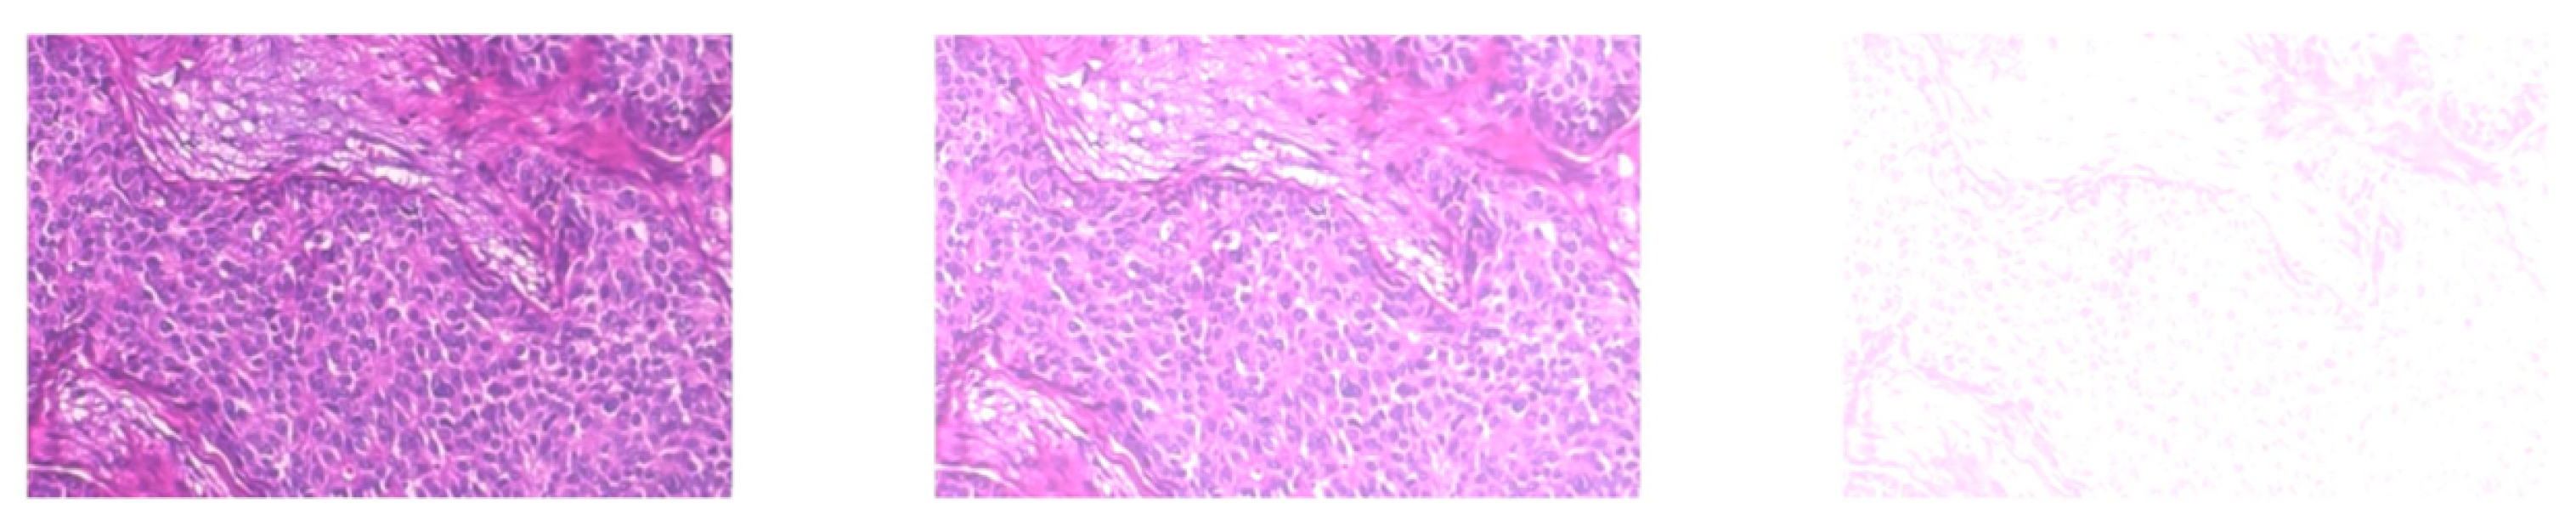

3.1. Step 1: Histopathological Image Pre-Processing